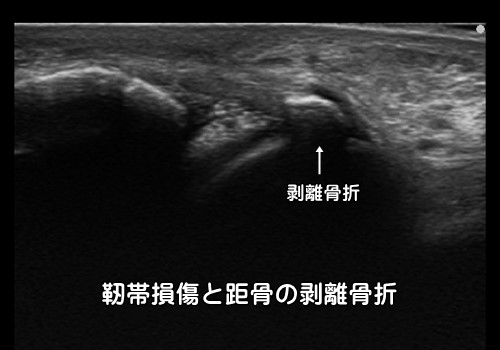

また靭帯に引っ張られることにより裂離骨折(れつりこっせつ)を起こす場合もあります。

内返し捻挫での腓骨の裂離骨折の割合

10歳以下:77% 11~14歳:19% 15~18歳:13%

年齢が低い程、靭帯の断裂よりも裂離骨折を起こします。

靭帯の強度よりも骨の強度の方が弱い小学生の足首の捻挫の7割は裂離骨折を伴います。